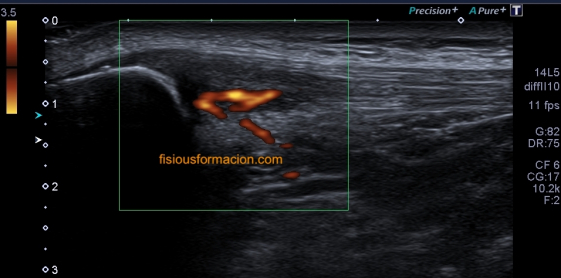

311. Doppler color y Modo Angio, dos secretos que igual no sabías.

Cuando realizamos una exploración ecográfica, el protocolo que sea, no es raro que uno de los comandos que más usemos sea el Doppler, sabemos cómo funciona el Doppler, Alejandro lo ha explicado en este blog y el libro Eco Fácil de Marbán, pero yo quiero contarte dos secretos, que seguro que sabes, pero que quiero contarlo por si hay alguien un poquito más rezagado que aún no se ha enterado.

Quiero que te preguntes si sabrías diferenciar entre una imagen Doppler Color y una imagen en Modo Angio o Doppler Power. Vas a decir que sí, que lo sabes. Y es cierto, en la mayoría de las ocasiones distinguimos estas dos técnicas por el color, una rojo y azul, otra azul o morado, u otras coloraciones según la casa comercial.

Modo Doppler Color

Modo Angio o Doppler Power

Ahora quiero que te preguntes si sabrías decirte que magnitud de la onda ultrasonográfica toma de referencia cada una de los dos comando cuando los activamos para darnos la imagen que estamos buscando…igual aquí tienes alguna dificultad, igual aquí, te he pillado¿Te sonríes?…me encanta…ah que ya lo sabes…bueno, pues lo voy a explicar para quien no lo sepa.

En la onda ultrosonográfica hay dos magnitudes claves, la longitud de onda, que es la distancia entre dos puntos de una misma onda, por ejemplo, entre sus valles o entre sus crestas, que será menor cuanto más alta sea la frecuencia, y la amplitud de la onda que es la máxima distancia que alcanza la onda, o de otro modo, lo enérgica que es esa onda.

Muy bien, en el Doppler Color (CDI) la magnitud de referencia que tomará nuestro equipo para hacer la medición de aquello que estemos interesados en estudiar será la longitud de onda. Sin embargo, en el Doppler Power o Modo Angio (Power) el equipo lee la Amplitud de la onda ultrasonográfica, la imagen de abajo.

Otra de las diferencias entre estos modos de trabajo si lo quieres llamar así es la medición de los hematíes. Me explico, cuando estamos haciendo Doppler lo que medimos es el movimiento hístico. No estamos midiendo las características ecográficas del tejido, es decir, no queremos saber si es anecoico, hipo o hiperecogénico, estamos midiendo su movimiento, el de los vasos, o el de las estructuras que puedan estar vascularizadas.

Por tanto este modo de trabajo valoriza el movimientos de los hematíes, su velocidad, y la densidad de estas células sanguíneas las mide el modo angio, por eso el Doppler color se usa para flujos rápidos (medidad cuantitativa) y el modo angio para flujos lentos (medida cualitativa), por eso el modo angio es mas sensible, así que si eres muy sensible, eres modo angio… ¿lo entiendes?